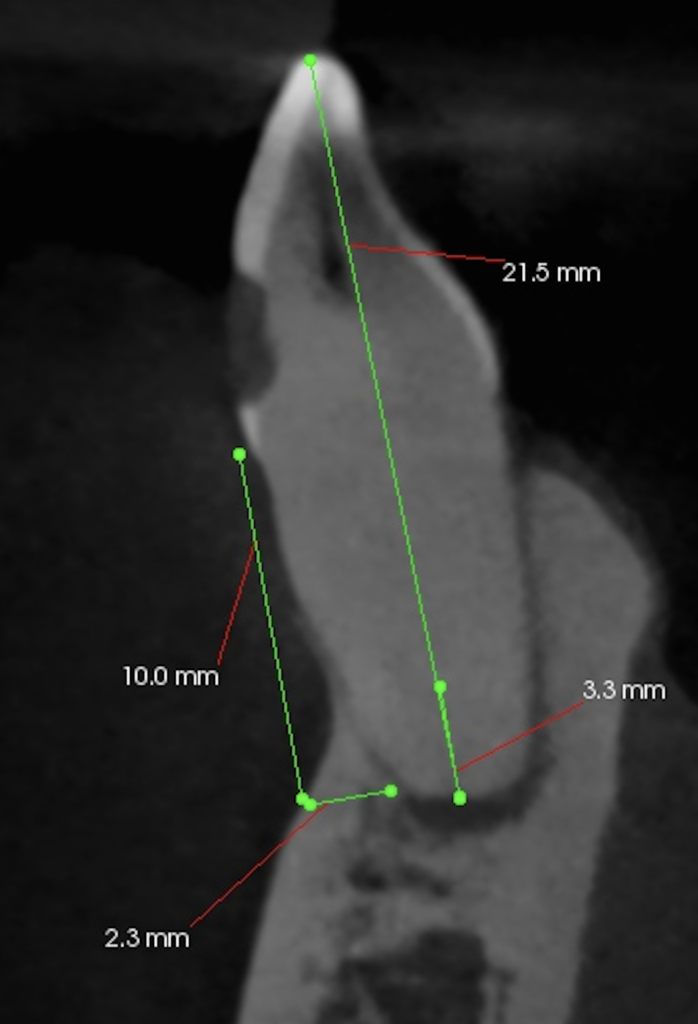

根管治療だがCBCTによれば、

切端からApexまで約25mmだ。

根尖部を3mm切断した。

逆根管形成・逆根管充填した。

PAを撮影した。

問題はないだろう。

術後にPA, CBCTを撮影した。